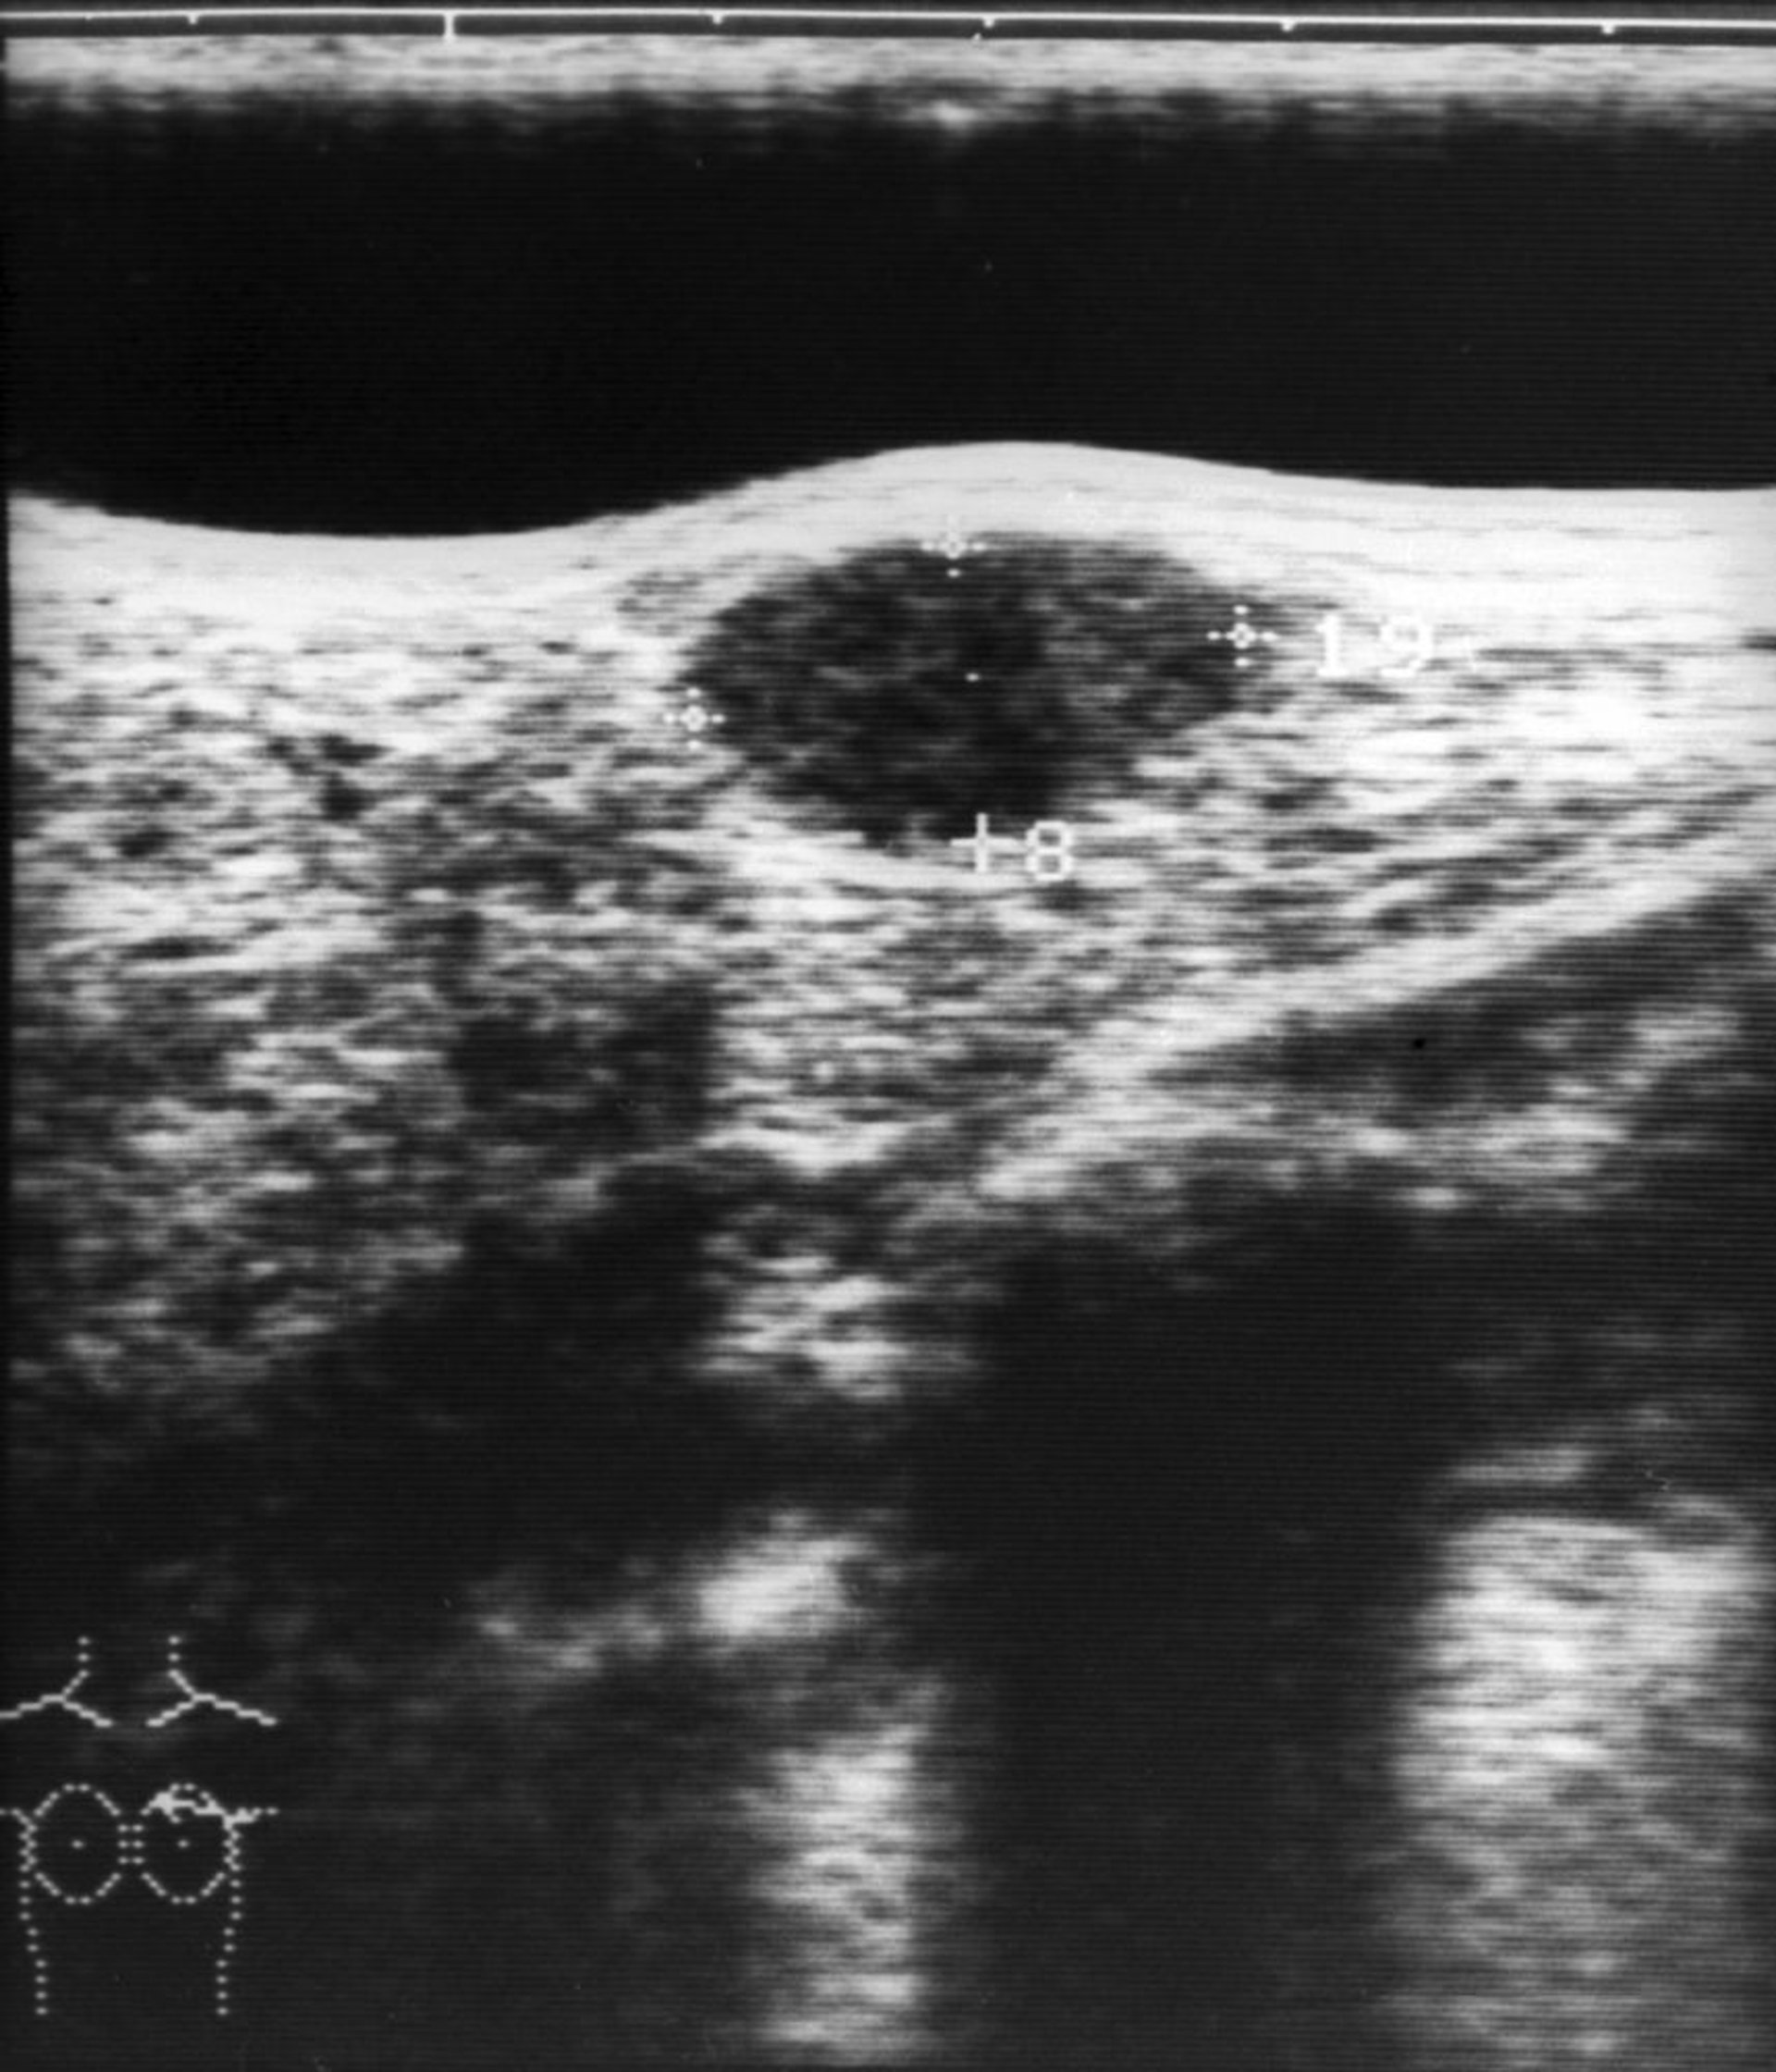

Cette image montre une échographie d'un fibroadénome du sein (structure hypoéchogène ovale dans le centre supérieur de l'image).

ZEPHYR/SCIENCE PHOTO LIBRARY